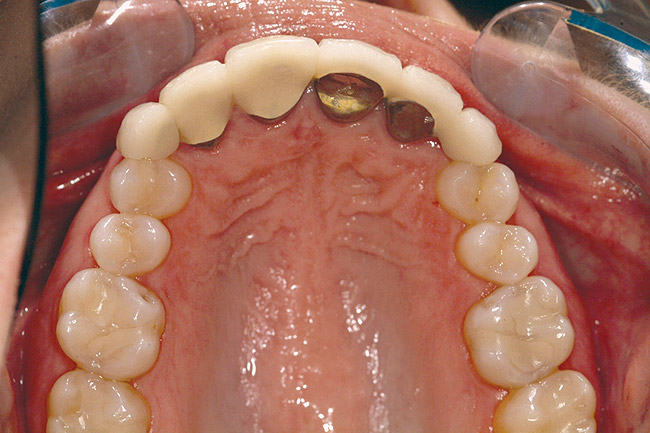

Fig 6 (and Fig 7). Prerestorative orthodontics was completed in 5 months. Final result 3 years, 4 months after completion.

Figure 6

Fig 8 (and Fig 9). Teeth Nos. 5 and 12 were converted to Nos. 6 and 11, and Nos. 6 and 11 were converted to Nos. 7 and 10. Nos. 4 and 13 were enlarged. Note stability and absence of orthodontic relapse. Before-and-after smiles. Periodontist: Edward P. Allen, DDS, PhD. Prosthodontist: Robert R. Winter, DDS.

Figure 8